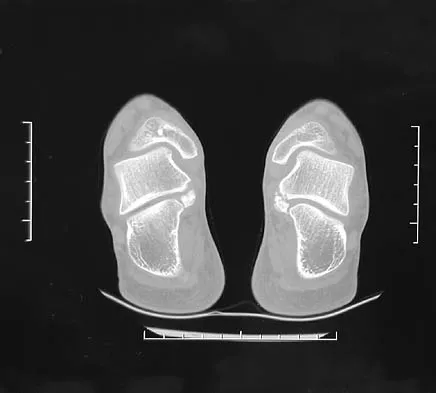

The mother of a 3-month-old infant states that she has difficulty positioning the infant's legs during diaper changes. Examination reveals limited abduction of both hips and a negative Ortolani sign. A radiograph reveals bilaterally dislocated hips. Initial management consists of guided reduction in a Pavlik harness, with weekly follow-up. Figures 57a and 57b show the radiograph and CT scan obtained after 6 weeks in the harness. Management should now consist of